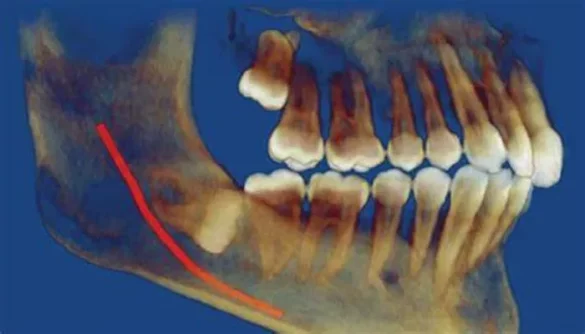

An impacted tooth is one that has not been able to break through the gum line properly. This can occur for various reasons, such as a lack of space in the mouth, incorrect angulation of the tooth, or a blockage caused by other teeth. Most often, impacted teeth are associated with the third molars (wisdom teeth), which are the last set of molars located at the back of the mouth. However, other teeth can also become impacted.

Tooth Angle: The tooth may grow at an incorrect angle, making it difficult for it to emerge properly through the gums.

Blockage: Other teeth or bone structures can block the pathway of an incoming tooth, preventing it from emerging.